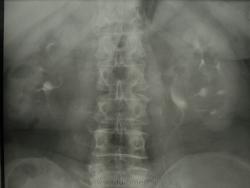

экскреторная урография

женщина 1941 г.р. на УЗИ гидронефроз обеих почек, Ваше мнение уважаемые коллеги.

Конечно диагноз уже известен.(доказан другими методами и вероятно давно)Я думаю что здесь поликистоз почек.

Поликистоз почек - это нечно иное...а вот о крупной парапельвикальной кисте слева и о парапельвикальных и паракаликальных кистах справа (несколько, но поменьше размерами) говорить необходимо. Естественно, классическая УЗ-ошибка - гидронефроз и крупные парапельвикальные кисты. Для того в\в урография и расставляет точки...как в данном случае.

спасибо всем за Ваши мнения, урографию делаем ну очень редко, как свалятся на голову и незнаю что делать, а в анамнезе и правда кисты почек (когда то давно делали Узи).